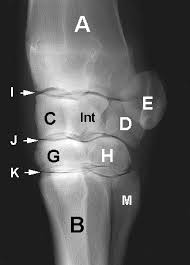

Carpal Bones Wikipedia from upload.wikimedia.org Drag the slider over the image to reveal or remove the highlighted bones of the radiograph labels: Only the proximal carpal bones are labeled and the distal ulna and radius. Pa radiograph of the wrist. Articulates with ulnar carpal bone. Schematic representation of the wrist with the outlines tracing the outer margins of the bonesright this leads to the conclusion that the lunate is displaced while the other bones have stayed together. They are usually divided into two rows: (a) distal phalanx 1st digit, (b) interphalangeal joint, (c) proximal phalanx 1st digit. Start studying carpal bones labeling anatomy.

I Examination Of The Wrist Surface Anatomy Of The Carpal Bones Sciencedirect from ars.els-cdn.com They are usually divided into two rows: If an abnormal alignment of the carpal bones is depicted during imaging of the. Start studying carpal bones labeling anatomy. (a) distal phalanx 1st digit, (b) interphalangeal joint, (c) proximal phalanx 1st digit. The carpal bones, also known as the carpus (plural: Capitate and all other carpal bones lie posterior to lunate on lateral radiograph. The carpal bones are the eight bones of the wrist that form the articulation of the forearm with the hand. The distal row articulates with the bases of the metacarpal bones forming the pa hand radiograph above have the following structures labeled:

The carpal bones are a group of eight, irregularly shaped bones carpal bones labeled. Drag the slider over the image to reveal or remove the highlighted bones of the radiograph labels: